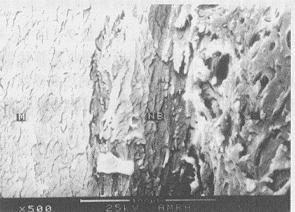

新骨在扫描电镜下显示较致密板层结构,与羟基磷灰石无纤维组织间隔(图3)。新骨组织的X线能谱分析显示钙磷元素含量与基骨组织相同。

图3 扫描电镜下术后24周实验组新骨与HA界面

Fig.3 Interface of new bone and HA 24 weeks after operation in experimental group under scanning of electronic microscope New bone integrated directly with HA (×500)